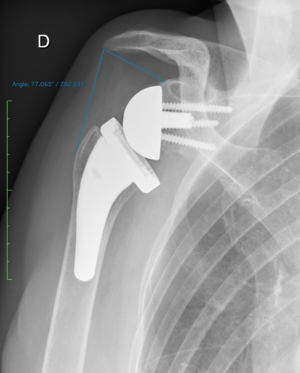

The distalization shoulder angle (DSA) angle is formed by a line connecting the most lateral border of the acromion and the superior glenoid tubercle and a line connecting the superior glenoid tubercle and the most superior border of the greater tuberosity. In this case, it is measured at 61 degrees.

The lateralization shoulder angle is formed by a line connecting the superior glenoid tubercle and the most lateral border of the acromion and a line connecting the most lateral border of the acromion and the most lateral border of the greater tuberosity. In this case, it is measured at 77 degrees.